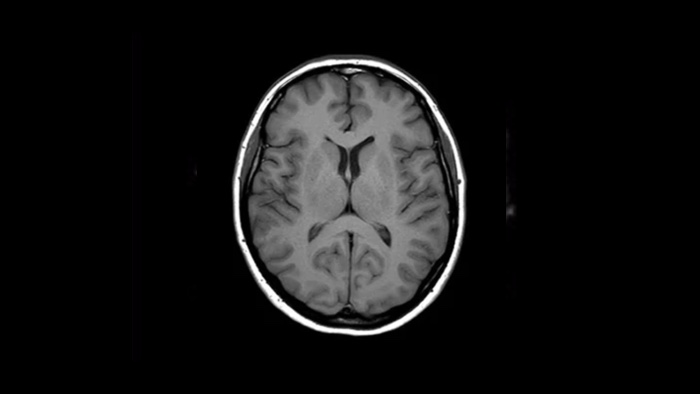

Ahora puede tenerlo todo con Ingenia Ambition. Ofrece la oportunidad de mejorar sus imágenes de resonancia magnética en todos los niveles.

Confianza diagnóstica Ofrece una resolución espacial hasta un 60% más alta en el mismo tiempo de escaneo. 4

Confianza diagnóstica Amplíe su capacidad de obtener imágenes excelentes en todas las áreas clínicas. Vea cómo se benefician sus compañeros.